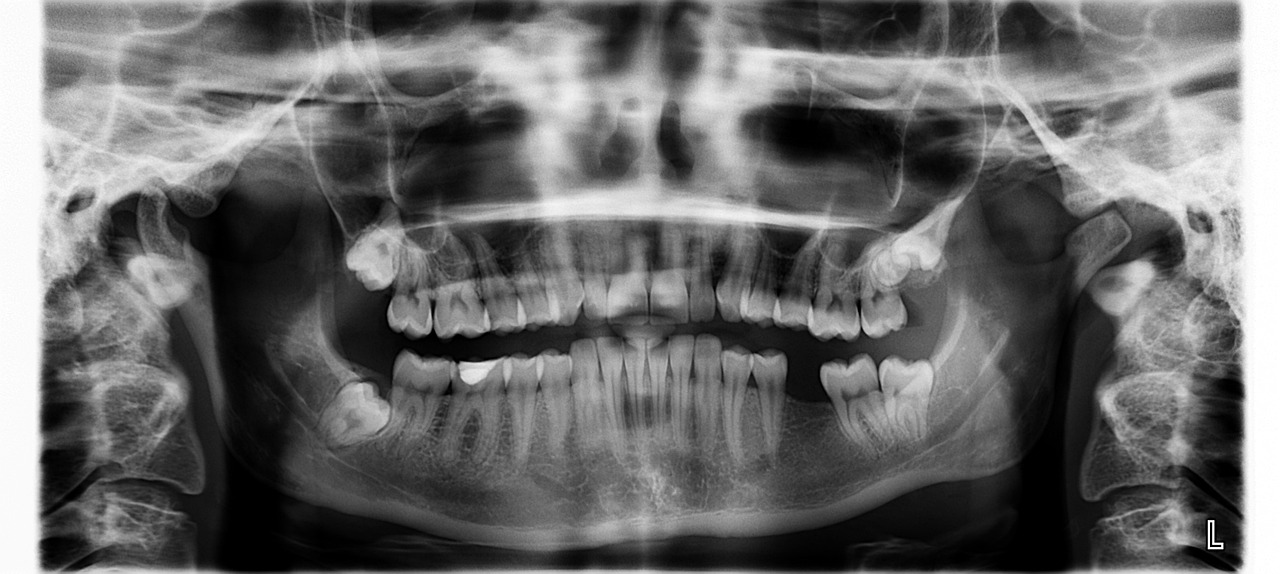

dark spots on X-ray